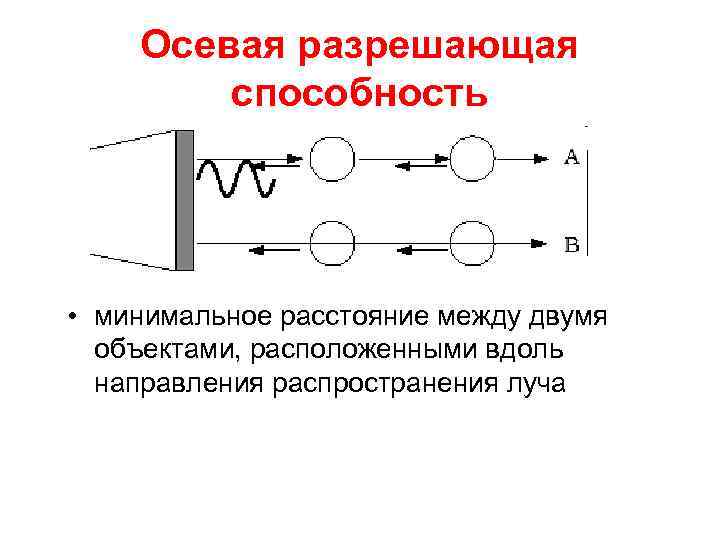

Осевая разрешающая способность • минимальное расстояние между двумя объектами, расположенными вдоль направления распространения луча

Осевая разрешающая способность • минимальное расстояние между двумя объектами, расположенными вдоль направления распространения луча